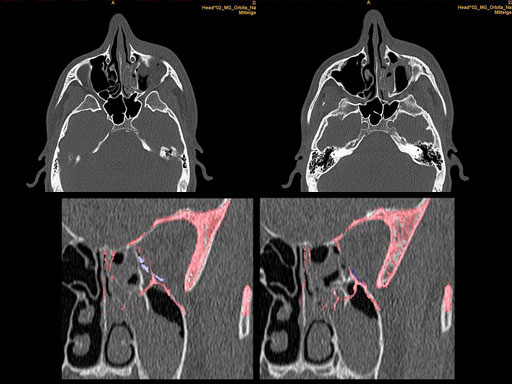

Furthermore, as orbital floor fractures are quite frequently associated with medial wall fractures; anatomic restoration especially in the transition zone between both wall is a demanding procedure. As described by B. Hammer, the orbital floor has an initial shallow convex section behind the rim, then inclines upward behind the globe, and inclines upward to meet the medial wall, creating a distinct bulge behind the globe. These convex curves of the medial wall and floor create a postbulbar constriction of the orbital cavity, which must be reconstructed when the orbit is rebuilt following fractures. Treatment is directed at precise anatomical reconstruction of orbital shape and volume in order to restore the correct position of the eye. To provide surgeons with an adequate implant that addresses the requirements of two wall acute orbital fractures or for secondary reconstruction of enophthalmos and dystopia, a new series of preformed orbital plates was developed for the new orbital matrix system.

These pre-formed orbital plates were developed based on the evaluation of more than 3000 CT scans of patient data and then reduced to 279 in order to find anatomical averages. In the end it was possible to reduce the number of plates down to two per side and still match the vast majority of all patients including males and females.

Unlike the existing two-dimensional mesh implants, the geometry of the new preformed plates will be adequate to match the individual anatomic situation of the patient in almost any case. However, the mesh parts can be individually adjusted if necessary. In these cases the solid part in the central posterior area needs to remain untouched. Areas of the orbit that do not require a bridging can be spared out by trimming the implant along the designated cutting lines in the height of the medial wall and/or length of the orbital floor area. The lateral anterior part of the plate is intentionally pre-bent higher than the orbital rim anatomy to allow free plate movement during plate positioning.

30 year old male patient with fracture of left orbital floor and medial wall.

Provided by Dr Dr Marc C Metzger, Freiburg, Germany.